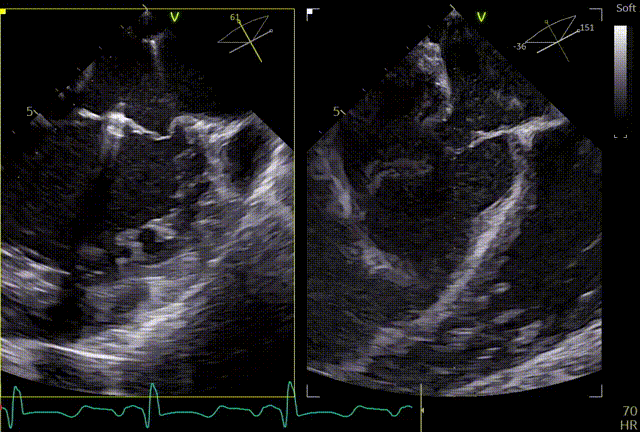

术前TEE及左房压

1区

1区带彩

2区

2区带彩

3区

3区带彩